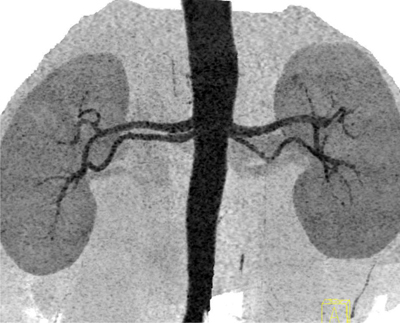

Figure 1.

Thick slab coronal inverted gray scala MIP image depicts bilateral double renal arteries, originating close to each other from the aorta and coursing almost parallel to each other towards renal hilum.